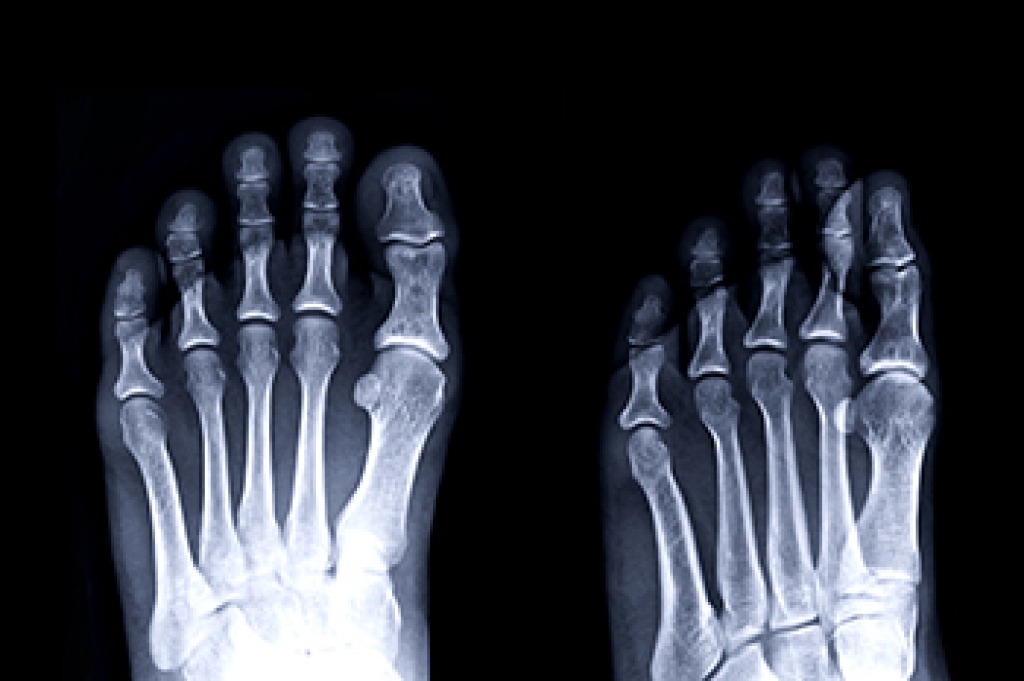

The fifth metatarsal is the long bone on the outer edge of the foot that connects to the little toe. Fractures in this bone are common and often occur from twisting the foot, direct impact, or overuse. There are two main types of fractures in this area. An avulsion fracture happens when a small piece of bone is pulled off by a tendon or ligament. A Jones fracture is more serious and occurs further along the bone, often requiring more time to heal. Symptoms include pain, swelling, bruising, and difficulty walking. Immediate care includes rest, elevation, and avoiding pressure on the foot. Some cases heal with wearing supportive footwear, while others may need a cast or even surgery. If you suspect you have injured the outside of your foot or feel sharp pain when bearing weight, it is suggested that you visit a podiatrist for a proper diagnosis and recovery plan.

A broken foot is caused by one of the bones in the foot typically breaking when bended, crushed, or stretched beyond its natural capabilities. Usually the location of the fracture indicates how the break occurred, whether it was through an object, fall, or any other type of injury.

Those that suspect they have a broken foot shoot seek urgent medical attention where a medical professional could diagnose the severity.

Treatment for broken bones varies depending on the cause, severity and location. Some will require the use of splints, casts or crutches while others could even involve surgery to repair the broken bones. Personal care includes the use of ice and keeping the foot stabilized and elevated.